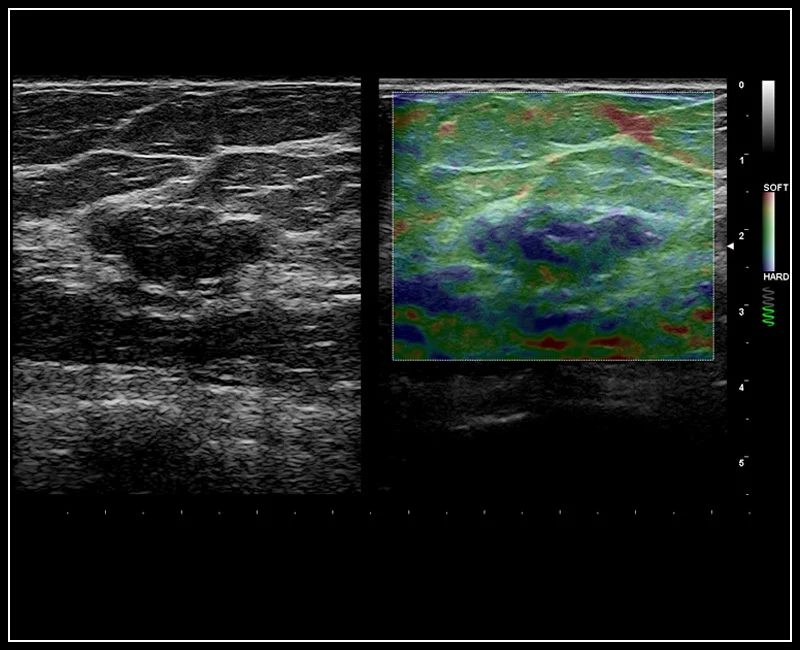

MyLab™9 Platform - Dual ElaXto characterization on breast lesion

MyLab™9 Platform - Dual ElaXto characterization on breast lesion